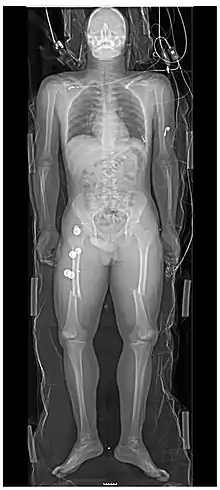

Les personnes ayant subi un traumatisme majeur ont souvent des radiographies du thorax et du bassin[22] et, selon le mécanisme de la blessure et la présentation, une évaluation ciblée avec échographie à la recherche d'hémorragie interne (FAST écho : focused assessment with sonography for trauma). Pour ceux qui ont une pression artérielle, une fréquence cardiaque et une saturation en oxygène relativement stables, les tomodensitogrammes sont utiles. Les tomodensitogrammes du corps entier, appelés body-scan, améliorent le taux de survie de ceux qui ont subi un traumatisme majeu[23],[24]. Ces scanners du corps entier (ou body-scan) utilisent des injections intraveineuses par produit de contraste (agent radioactif)[25]. On craint que l'administration de produit de contraste intraveineux dans des situations de traumatisme sans confirmation d'une fonction rénale adéquate puisse endommager les reins, mais cela ne semble pas être significatif[26].